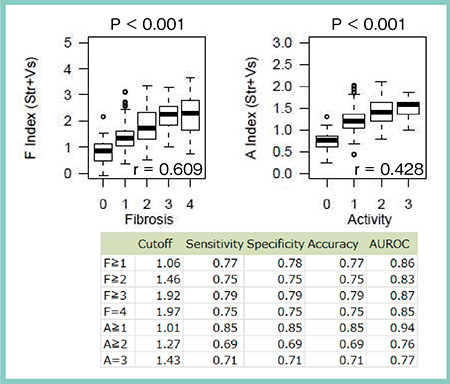

対象は,2015年7月〜2017年3月に肝生検を施行した慢性肝疾患353名,臨床的肝硬変13名,健常者22名の計388名で,肝生検と同時にSWMおよびRTEを実施した。病理所見による線維化ステージは,線維化なし(F0)が55名,軽度の線維化(F1)が182名,肝硬変(F4)が32名であった。SWMのVs値と病理所見を比較すると,線維化の悪化に伴いVs値が上昇する明らかな相関が見られ(図2),線維化の程度を非侵襲的かつ定量的に予測可能であった。肝硬変におけるVs値のカットオフ値は1.67m/sで,前述の症例は2.06m/sであることから肝硬変であると推測できる。さらに,SWMとRTEの計測値を基に,線維化を推定するfibrosis index(F index)と炎症を推定するactivity index(A index)を算出し,病理所見と比較したところ,やはり線維化ステージの上昇に伴いF index,A index共に上昇した(図3)。

図3 F index,A indexと病理所見による線維化ステージとの比較5)